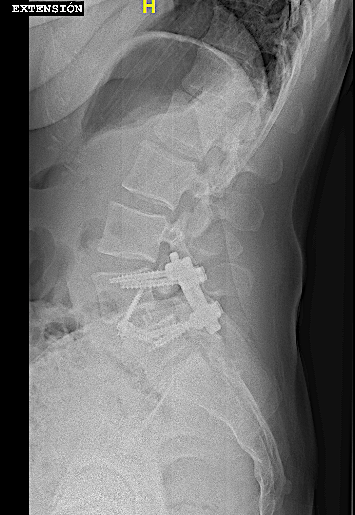

Obsérvese el incremento de la lisis de la pars en las RX dinámicas. La paciente no presentaba clínica radicular significativa por lo que se optó por ALIF L5-L6. El disco L4-L5 presentaba un grado bajo de degeneración.

Tras retirada de faja, la paciente seguía presentando lumbalgia mecánica. Obsérvese la lisie de la pars.

Tras la fijación percutánea, la paciente seguía presentando lumbalgia mecánica (de menor intensidad). Tras agotar opciones de tratamiento conservador, atribuimos como causa la discopatía incipiente L4-L5 (que había progresado).